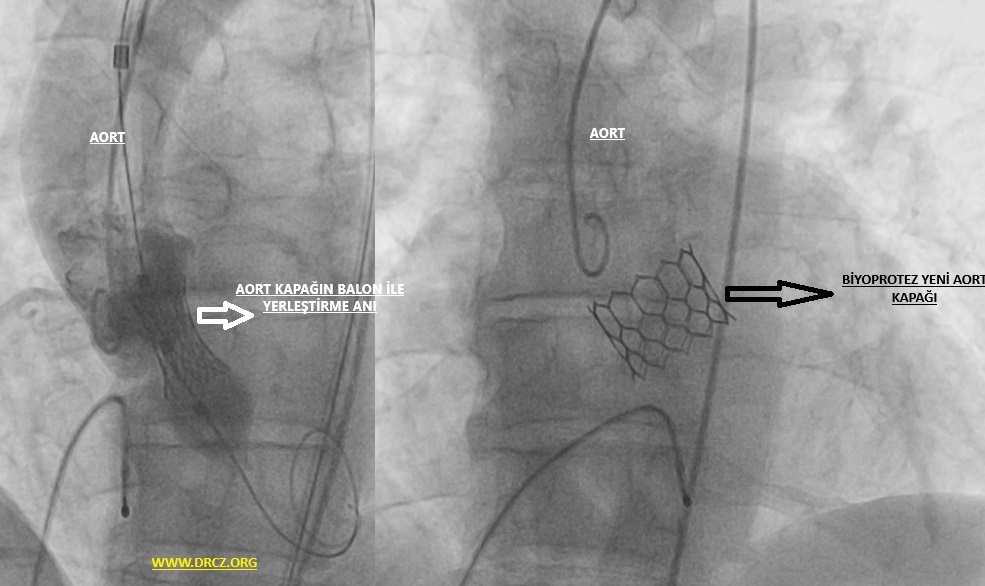

TAVI, transkateter aort kapak yerleştirme işleminin tıbbi kısaltmasıdır. Tam olarak açılamayan – kireçlenerek esnekliğini yitiren bir aort kapağının üzerine yeni kapak yerleştirerek kalbinizden aorta giden kan akımını iyileştirir ve kalbin iş yükünü ciddi oranda azaltır.

Resim 1: Göğüs Tomografisinde görülen aort kapaktaki kireçlenme (kalsifikasyon)

TAVI genellikle derin sedasyon ya da genel anestezi ile yapılan – kasıktaki atardamardan küçük bir kesi ile yapılan ağrısız bir işlemdir. Koroner anjiyografi veya stent işleminden kullanılan kateterlere benzeyen dar ve esnek bir tüp (katater)kasıkta bulunan atardamarınıza yerleştirilir ve kalbinizdeki aort kapağınıza ulaşılır. Bu kateter esnekliğini yitirmiş ve kireçli eski kapağınızın üstüne yedek bir kapak takmak için kullanılır. Bu katerterden geçen sistem ile ameliyata gerek kalmadan yeni biyoprotez kapak eskimiş kapağın üzerine yerleştirilir.